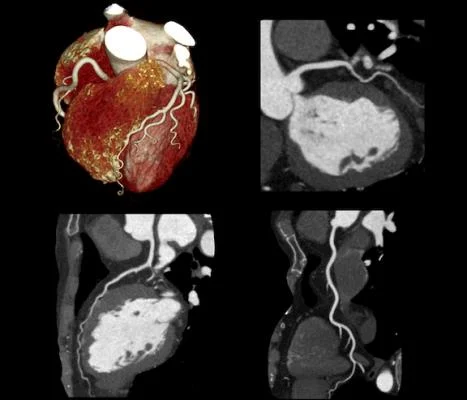

Whole-body CT Angiography is an imaging scan that is used to examine the functioning of the whole body's blood vessels and arteries. It depicts all vascular regions of the body in a single procedure within a short period. This scan detects various blood vessel-related ailments such as narrowing and fat deposition in the arteries. For the procedure of Whole-body CT Angiography, you will be injected with contrast media to obtain cross-sectional images of the vessels.

This scan is helpful for doctors to observe the blood vessels for blockages, clots, aneurysms, congenital cardiovascular abnormalities, disorganized blood vessels, tumours, vessel ruptures, or injuries.